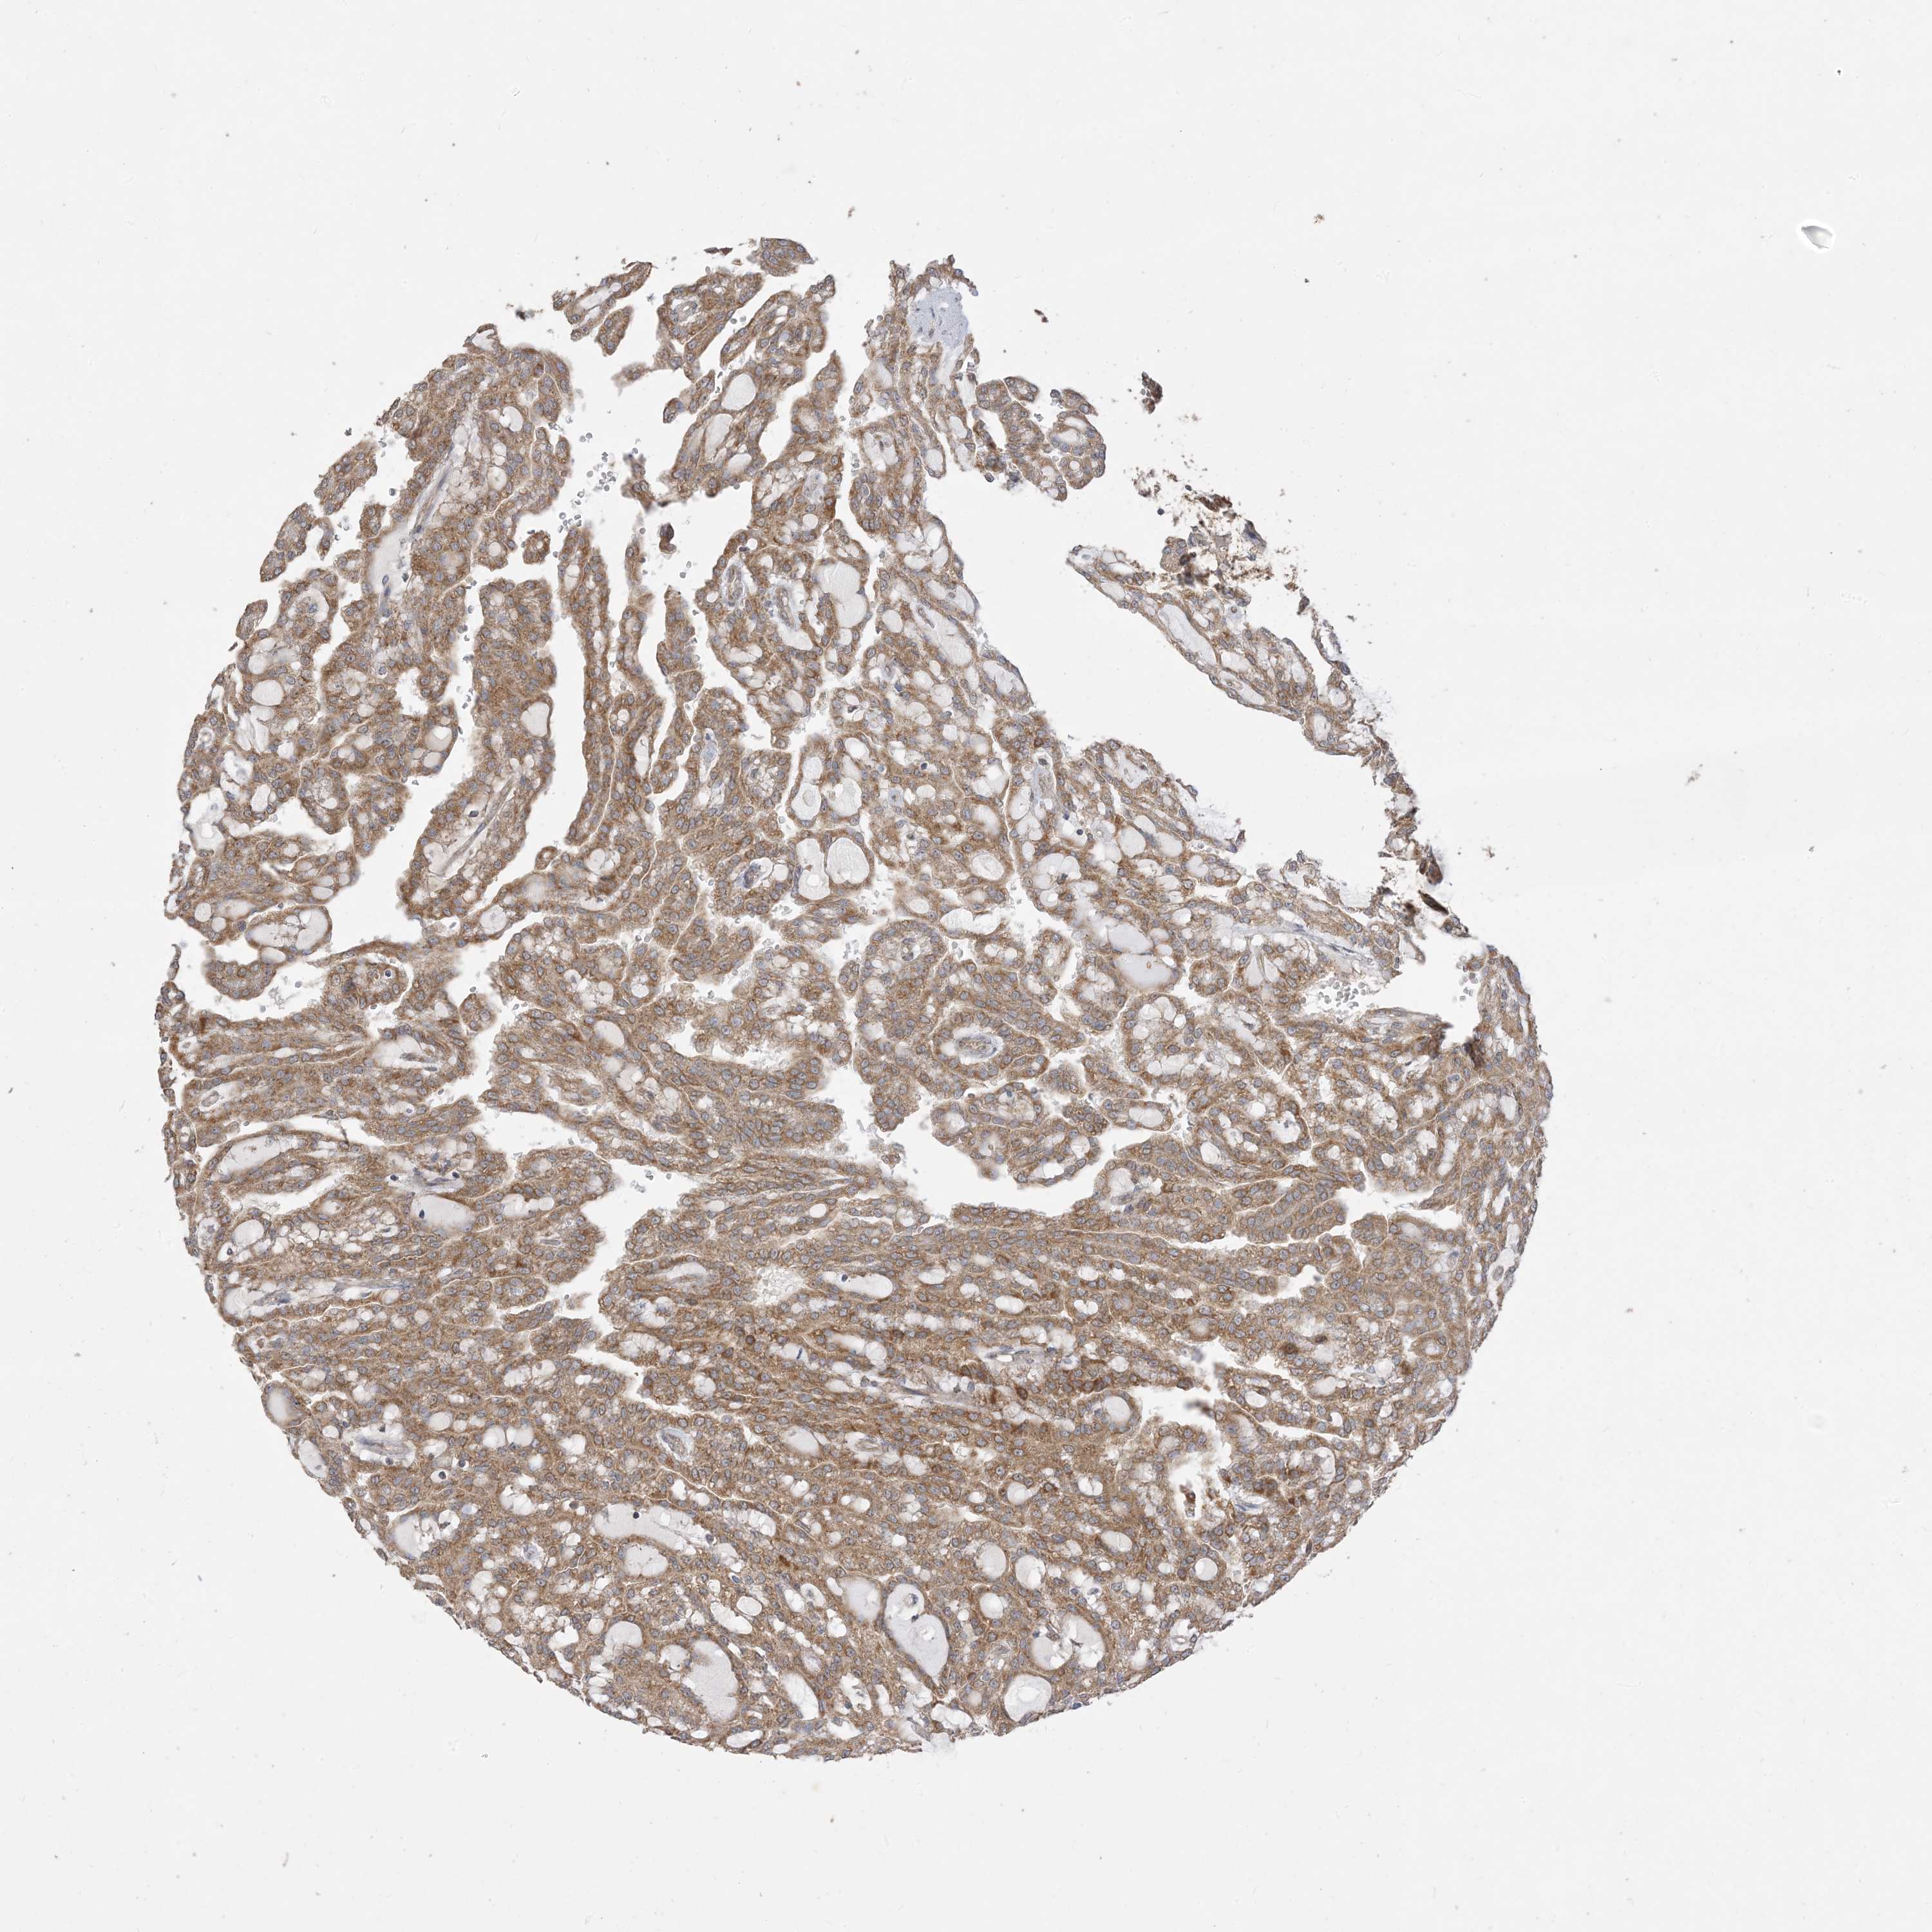

KIDNEY RENAL PAPILLARY CELL CARCINOMA (TCGA) - Interactive survival scatter ploti

The Survival Scatter plot shows the clinical status (i.e. dead or alive) for all individuals in the patient cohort, based on the same data that underlies the corresponding Kaplan-Meier plots. Patients that are alive at last time for follow-up are shown in blue and patients who have died during the study are shown in red.

The x-axis shows the expression levels (FPKM) of the investigated gene in the tumor tissue at the time of diagnosis. The y-axis shows the follow-up time after diagnosis (years). Both axes are complimented with kernel density curves demonstrating the data density over the axes. The top density plot shows the expression levels (FPKM) distribution among dead (red) and alive patients (blue). The right density plot shows the data density of the survived years of dead patients with high and low expression levels respectively, stratified using the cutoff indicated by the vertical dashed line through the Survival Scatter plot. This cutoff is automatically defined based on the FPKM cutoff that minimizes the p-score. The cutoff can be changed by dragging the vertical line or by entering a cutoff value in the square labeled "Current cut-off".

Under the Survival Scatter plot the p-score landscape (black curve; left axis) is shown together with dead median separation (red curve; right axis). Dead median separation is the difference in median mRNA expression between patients who have died with high and low expression, respectively. It is calculated as follows: median FPKM expression of dead patients with high expression - median FPKM expression of dead patients with low expression. This is intended to aid the user in visually exploring custom cutoffs and the associated p-scores and dead median separation.

Individual patient data is displayed and can be filtered by clicking on one or more of the category buttons on the top of the page. Categories describing expression level and patient information include: high, low, alive, dead, female, male and tumor stages. The scale of the x-axis can be toggled between linear and log-scale by clicking on the "x log" button. Mouse-over function shows TCGA ID, patient information and mRNA expression (FPKM) for each patient.

& Survival analysisi

Kaplan-Meier plots summarize results from analysis of correlation between mRNA expression level and patient survival. Patients were divided based on level of expression into one of the two groups "low" (under cut off) or "high" (over cut off). X-axis shows time for survival (years) and y-axis shows the probability of survival, where 1.0 corresponds to 100 percent.

SIRT3 is potential prognostic, high expression is favorable in Kidney Renal Papillary Cell Carcinoma (TCGA)